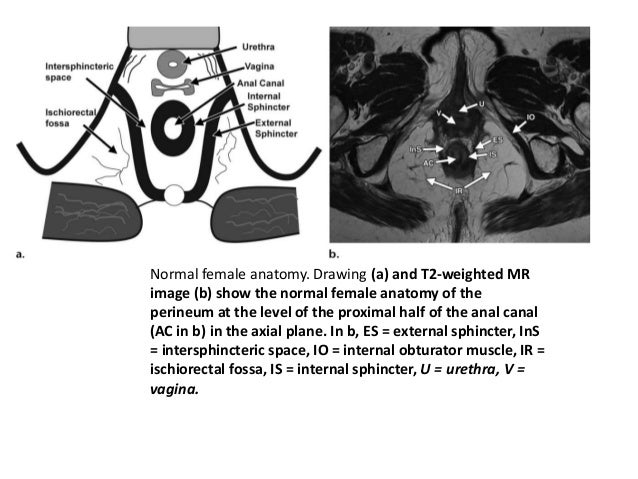

Perineum Anatomy Mri : The perineum is an anatomical region in the pelvis.